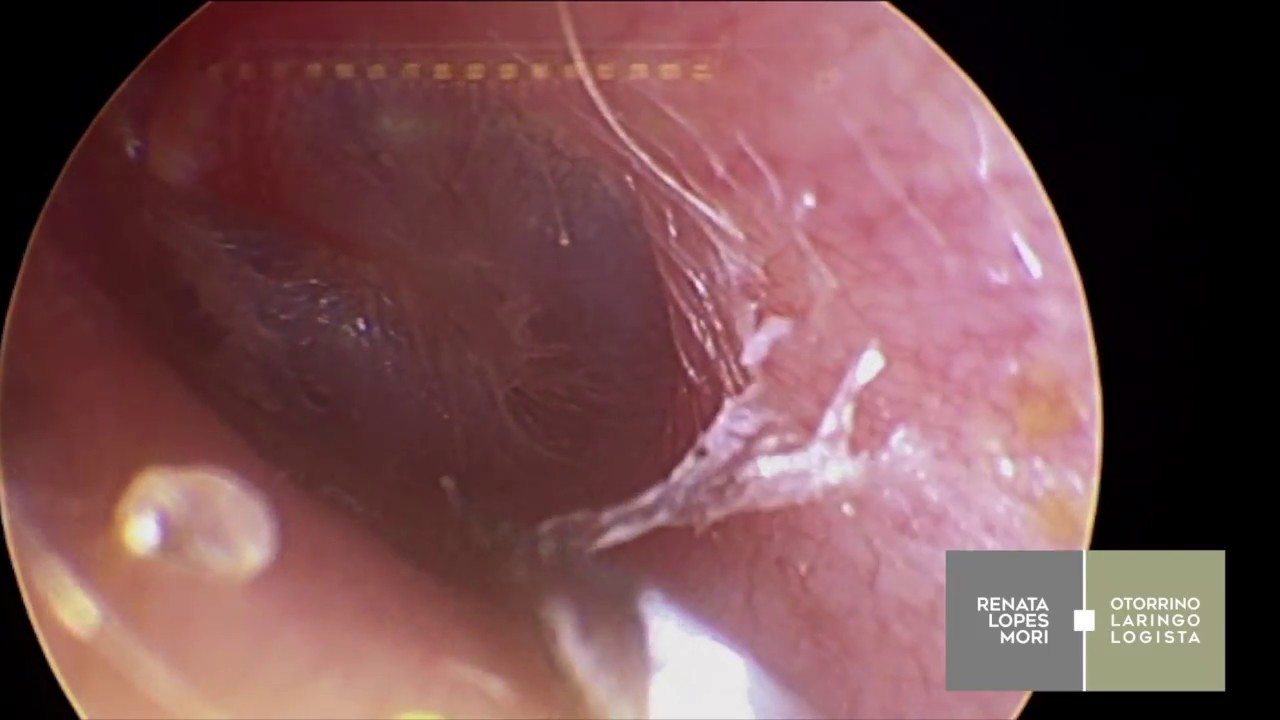

Cirurgia das amígdalas e da adenoide por vídeo - A2 + timpanotomia

Source: www.youtube.com 1280 x 720

.